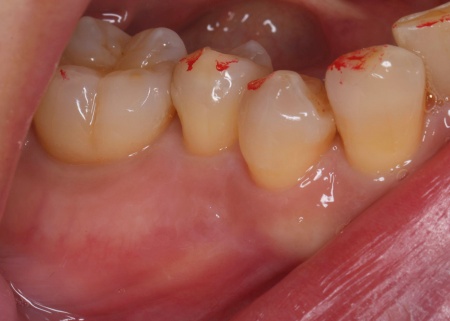

| 行ったご提案・治療内容 | 治療方法としては、いくつかの選択肢があります。 ①抜歯(歯を抜く治療) メリット:炎症の原因となっている歯を取り除くことができる デメリット:歯を失うため、その後にブリッジや入れ歯、インプラントなどで補う治療が必要になる ②精密な根管治療による保存治療 今回はできる限り歯を残すため、歯科用マイクロスコープを使用した精密な根管治療を提案しました。 それぞれの治療方法について丁寧にお伝えしたところ、精密な根管治療に同意いただきました。 まず右下奥歯を削り、歯の内部にある感染した組織を取り除きます。 |

治療後